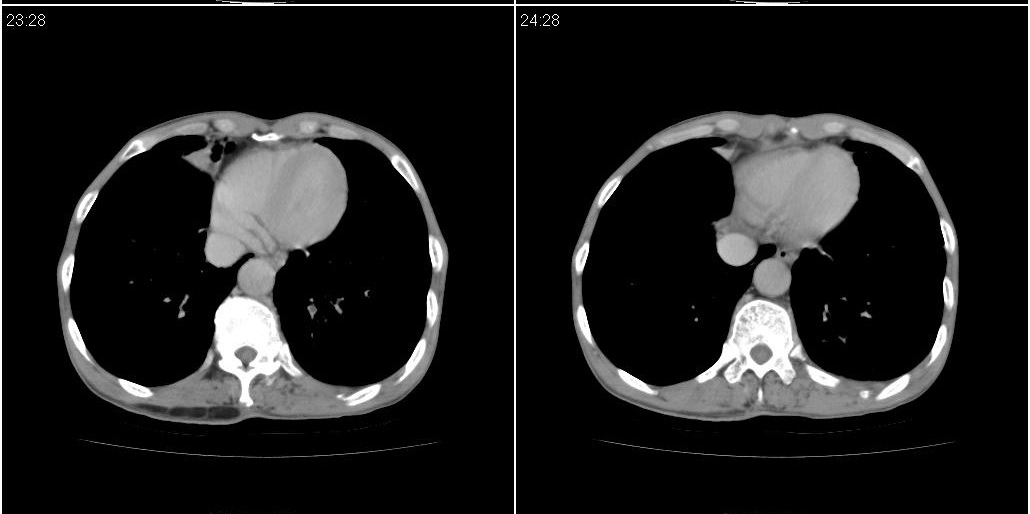

标题: ct增强:

[本贴已被 fanshl 于 2010-3-30 7:14:31 修改过]

作者: 施明 时间: 2010-3-30 16:07

炎性肿块

右肺中叶阻塞性不张及肺炎,高度怀疑支气管占位,建议纤支镜检查!

考虑右肺中叶感染。左肺下叶支扩。